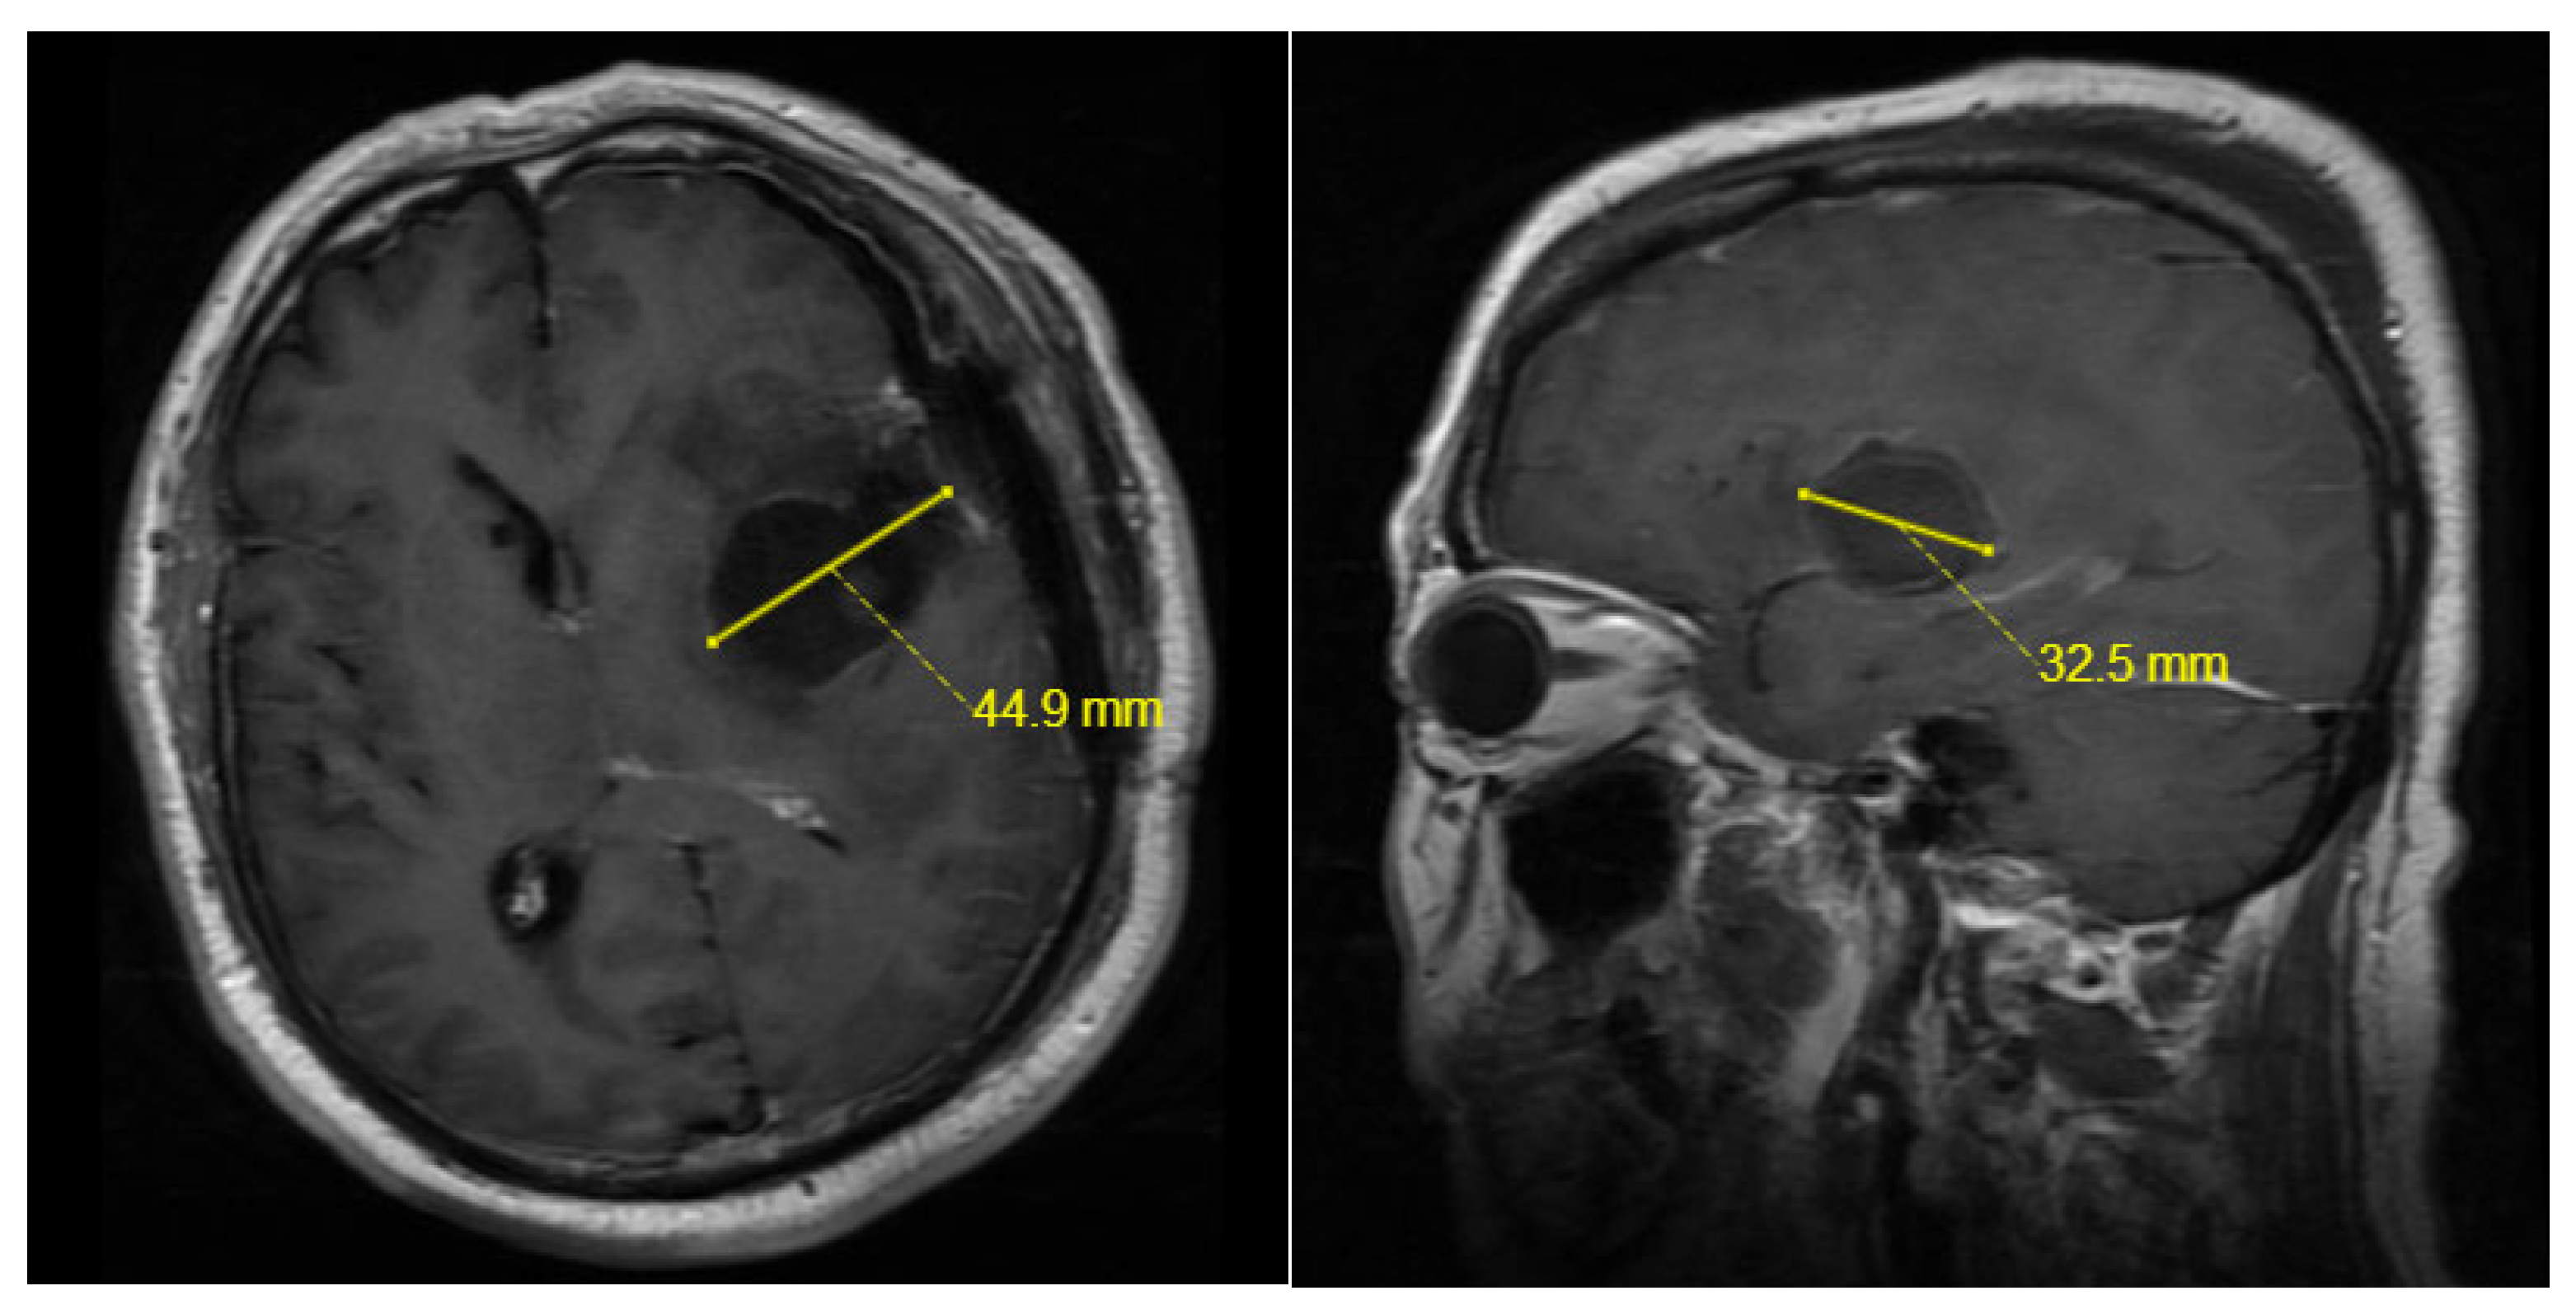

| Maximum Tumor Diameter(mm) | 41.60 [32.15, 55.00] | 49.50 [40.00, 60.00] | <0.01 |

| Post-op Maximum Cavity Diameter(mm) | 43.15 [33.77, 54.82] | 53.90 [46.90, 63.70] | <0.01 |